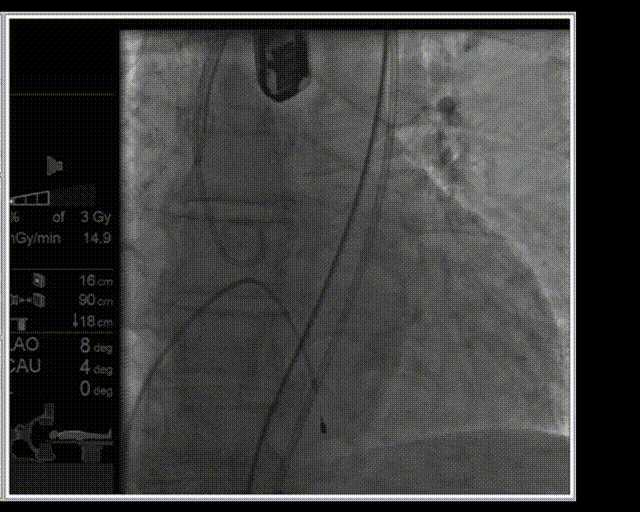

主动脉根部造影

18F球囊预扩

输送器顺畅过弓及跨瓣

瓣膜释放